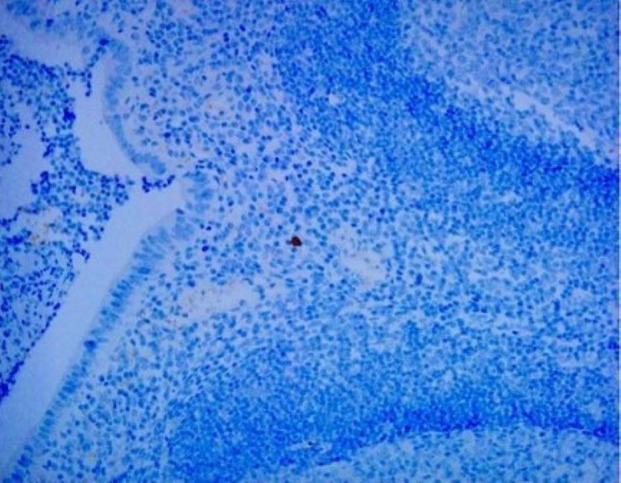

Methods: We retrospectively reviewed children<6 years of age with intussusception who underwent surgery for failed reduction. The pathological tissue was processed into formalin-fixed paraffin-embedded (FFPE) sections. Adenovirus immunohistochemistry (IHC) and PCR testing were performed to obtain direct evidence of the relationship between adenovirus infection and intussusception.

Results: Our study included 29 patients, 27 appendiceal and 8 intestinal tissues. Only eight appendix specimens were successfully processed into FFPE tissue. IHC testing was positive in three cases (37.5%), and PCR testing was positive for adenovirus type C in four cases (50%). The control group consisted of eight children <6 years who underwent incidental appendectomies, and all control subjects had negative IHC and PCR analyses. PCR is as useful and reliable as IHC in diagnosing adenovirus in intussusception and has greater sensitivity than IHC.

Conclusion: We directly confirmed the relationship between adenovirus infection and intussusception through IHC analysis and PCR detection of pathological evidence. PCR is more sensitive than IHC for diagnosing adenovirus in intussusception.